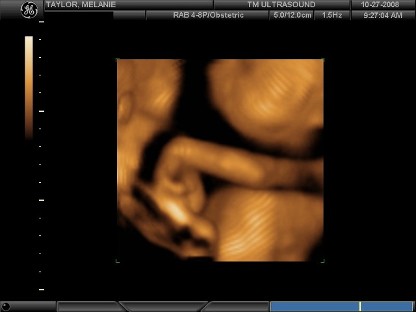

4D Sonogram

At 28 weeks Murad and I went to get a "4D Sonogram" done. I remember sitting there nervous, but excited. We went in and they began showing us Mikaela. There was her head, watching her mouth move... scanning down the technician stopped and said, "Did you know her arms are like that?" I immediately looked up and saw her hands were tucked. I replied "No...". She asked me to turn on my side to see if Mikaela would wake up from her nap and move her arms. I remember Murad wiping away my tears saying everything's ok. But she stayed sleeping and I'll never forget that day. Our whole world was turned upside down and that is where it all began. But l

ittle did we know the wonderful world it would lead us to! Here are some of the pictures I thought I'd share with all of you.